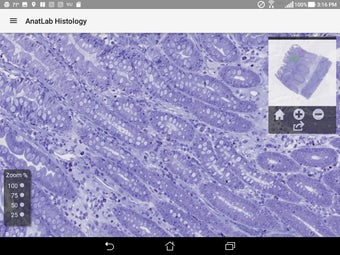

AnatLab Histology es una aplicación gratuita para Android desarrollada por Eolas Technologies Inc. que proporciona a los usuarios imágenes de diapositivas microscópicas de ultra alta resolución. Esta aplicación es una herramienta ideal para estudiantes, profesores, investigadores y el público en general. Con esta aplicación, pueden explorar el paisaje microscópico completo del cuerpo como si estuvieran mirando una colección de diapositivas reales en un microscopio físico. Tiene una función basada en la nube, la aplicación se puede acceder en cualquier dispositivo móvil Android, lo que la hace muy conveniente y accesible.

La aplicación ofrece una colección completa de imágenes de diapositivas microscópicas de histología que se pueden ver en ultra alta resolución. Las imágenes son de calidad excepcional y proporcionan una representación precisa del paisaje microscópico del cuerpo. La aplicación es fácil de usar y navegar, lo que permite a los usuarios explorar diferentes partes del cuerpo con facilidad.